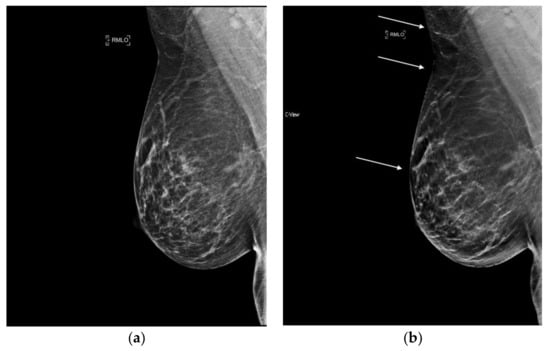

6.5. Artifacts

Awareness of a few artifacts unique to s2D can ease familiarization with synthesized images. A bright-band artifact may be observed with s2D as a layer of brighter tissue, which follows the curvature of the breast at the subcutaneous level. (Figure 6). Typically this area contains fatty tissue and lesion detection can still be made readily. Additionally, especially in very dense or very thick breasts, because higher radiation dose is needed, the detector can get saturated at the skin line and cause loss of resolution of the skin line. (Figure 7).

Figure 6.

Bright band artifact (indicated by arrows) can be seen along the curvature of the medial breast on synthesized mammography. (a) 2D FFDM (no artifact) (b) s2D with Bright band artifact.

Figure 7.

Loss of skin resolution or “skin burnout” (indicated by arrows) can be seen on synthesized mammography. (a) 2D FFDM (no artifact) (b) s2D with skin burnout artifact.